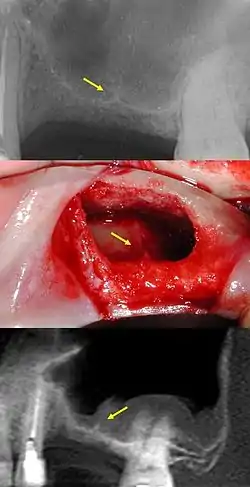

In anatomy, Underwood's septa (or maxillary sinus septa, singular septum)[1][2] are fin-shaped projections of bone that may exist in the maxillary sinus, first described in 1910 by Arthur S. Underwood, an anatomist at King's College in London.[3] The presence of septa at or near the floor of the sinus are of interest to the dental clinician when proposing or performing sinus floor elevation procedures because of an increased likelihood of surgical complications, such as tearing of the Schneiderian membrane.[4]

Primary vs. secondary septa

Recent studies have classified two types of maxillary sinus septa: primary and secondary. Primary septa are those initially described by Underwood and that form as a result of the floor of the sinus sinking along with the roots of erupting teeth; these primary septa are thus generally found in the sinus corresponding to the space between teeth, as explained by Underwood. Conversely, secondary septa form as a result of irregular pneumatization of the sinus following loss of maxillary posterior teeth.[6] Sinus pneumatization is a poorly understood phenomenon that results in an increased volume of the maxillary sinus, generally following maxillary posterior tooth loss, at the expense of the bone which used to house the roots of the maxillary posterior teeth.